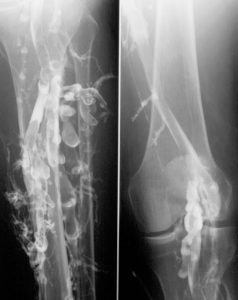

Sonntag, 07. August 2016 ab 13:30 Uhr: “Tiefe Venenthrombose” oder “TVT” ist ein Blutgerinnsel in den tiefen Venen der Beine. “Lungenembolie” oder “PE” ist solch ein Blutgerinnsel, die aber verdrängt wurde und in die Lunge gereist ist. TVT und PE zusammen werden in der Medizin als “Venöse Thromboembolie” bezeichnet. Venöse Thromboembolien können gefährlich sein und manchmal sogar zum Tod führen. Ein wichtiges Ziel der Behandlung bei Patienten mit Venöser Thromboembolie ist, eine zweite Venöse Thromboembolie zu vermeiden.